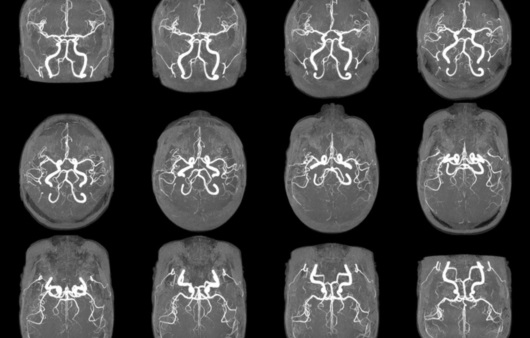

반면에 MRA는 혈관의 구조와 혈류를 시각화하는 데 집중된 기술입니다. 성공적인 심혈관 진단을 위해 혈관의 상태를 정확히 파악하는 것이 중요한데, MRA는 이러한 혈관 최적화 진단에 매우 효과적입니다. MRA는 MRI의 원리를 기반으로 하면서도, 특정한 혈관을 강조하여 더 잘 보기 위해 조영제를 사용하기도 합니다. 이로 인해, 의사는 혈관의 톤과 흐름을 보다 명확하게 관찰할 수 있으며, 협착증, 혈전, 기타 혈관 질병의 발견에 큰 도움을 줍니다. MRA와 MRI는 모두 안전한 검사 방법으로, 특히 방사선 노출이 없다는 점에서 의료진과 환자 모두에게 선호됩니다. 하지만 두 기술의 적용 분야와 사용하는 기법이 다르기 때문에 의사와 환자 모두가 각 기법의 특성을 잘 이해하고 활용하는 것이 중요합니다.

MRA의 주요 특징은 혈관을 중심으로 한 영상을 생성하며, 비침습적으로 혈관 질환을 평가할 수 있다는 점입니다. MRA는 주로 다음과 같은 상황에서 활용됩니다:

- 혈관의 협착이나 폐색을 진단: MRA는 동맥과 정맥을 자세히 시각화하여 혈관의 좁아진 부분이나 막힌 부분을 확인할 수 있게 해줍니다.

- 동맥류 및 기타 혈관 abnormality 조기에 발견: MRA는 암 투병 과정에서 혈관의 형태를 알 수 있게 하여, 동맥류와 같은 혈관 기형의 조기 발견에 매우 효과적입니다.

MRA의 장점 중 하나는 빠르고 비침습적이라는 것입니다. 검사 시간이 짧고, 환자가 검사 중 거의 활동을 하지 않아도 된다는 점에서 많은 사람들에게 여전히 편리함을 제공합니다. 또한, MRA는 다양한 조영제와 기술을 조합하여 각기 다른 유형의 혈관을 더욱 선명하게 보여주는 데에 도움을 줄 수 있습니다. 예를 들어, 특정한 조영제를 사용하게 되면 말초혈관의적절한 진단이 가능해지며, 이는 나쁜 혈류 상태를 진단하는 데 중요한 역할을 합니다.